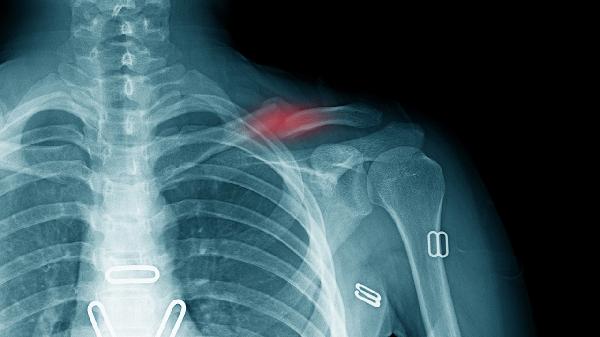

手术通过钢板螺钉内固定实现骨折端刚性稳定,尤其适用于粉碎性骨折或明显移位的情况。相比保守治疗,可降低畸形愈合概率约60%,但金属植入物可能造成局部异物感或应力遮挡效应。

约5-10%患者可能出现切口感染、神经损伤或内固定松动。糖尿病患者感染风险增加2倍,吸烟者骨不连发生率高达15%。术前需评估凝血功能及软组织条件。

手术治疗需经历切口愈合2周、骨痂形成6周及完全负重12周三阶段。虽然早期活动度更佳,但完全骨愈合时间与保守治疗无显著差异,均需3-6个月。

术后饮食应增加蛋白质和钙质摄入,每日补充500ml牛奶或等量豆制品促进骨愈合。康复期建议进行钟摆运动、爬墙训练等物理治疗,6周内避免提重物及剧烈运动。定期复查X线观察骨折线消失情况,内固定取出需根据骨愈合状况决定,通常术后12-18个月实施。注意观察切口红肿、异常疼痛等感染征兆,睡眠时垫高患肢减轻肿胀。